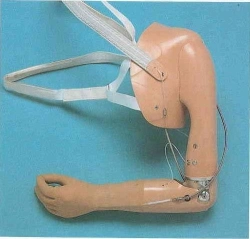

Предназначен для пользователей всех половозрастных групп, имеющих культю бедра на уровне верхней, средней и нижней трети.